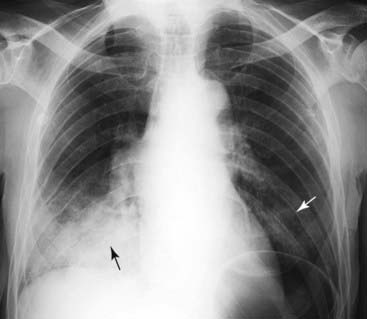

Figure 3-4 Silhouette sign, right middle lobe pneumonia.

A, Fluffy, indistinctly marginated airspace disease is seen to the right of the heart. It obscures the right heart border (solid black arrow) but not the right hemidiaphragm (dotted black arrow). This is called the silhouette sign and establishes that the disease (1) is in contact with the right heart border (which lies anteriorly in the chest) and (2) is the same radiographic density as the heart (fluid or soft tissue). Pneumonia fills the airspaces with an inflammatory exudate of fluid density. B, The area of the consolidation is indeed anterior, located in the right middle lobe, which is bound by the major fissure below (dotted white arrow) and the minor fissure above (solid white arrow).